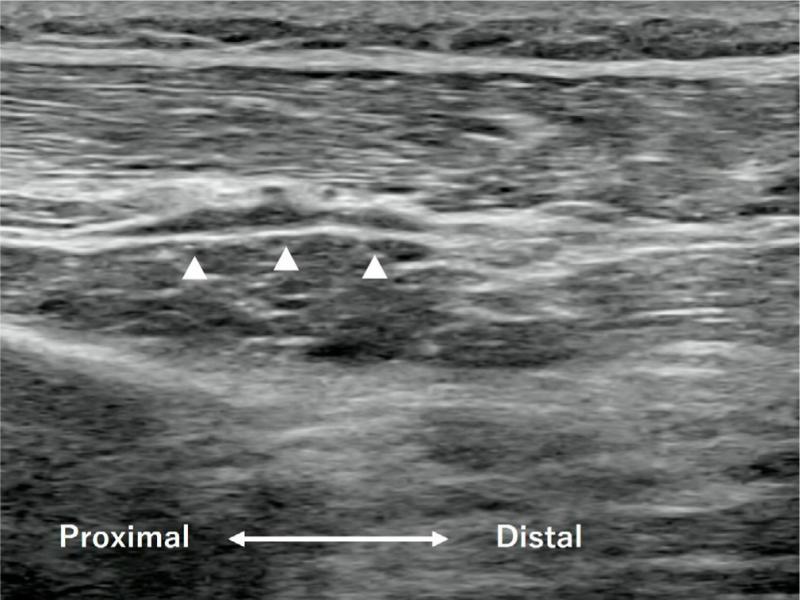

Fig. 4.

A longitudinal image of the proximal dorsal forearm 15 weeks after the first hydrodissection. The PIN appears quite swollen (arrowheads), but the multiple constrictions are no more evident

Perineural hydrodissection is a minimally invasive technique to dissect the perineural plane and tissue space. Currently, there are no high-level studies to determine the effectiveness of hydrodissection; however, low-level studies have demonstrated some effectiveness(35). In the present study, the patient’s symptom began five or more years previously, and 15 weeks after the first hydrodissection, the symptom was fully recovered, with ultrasonography depicting an improvement of the multiple stenotic lesions (Fig. 4). It is unlikely that this result occurred in a natural course, and we believe that this procedure contributed to separating the nerve from the surrounding tissue, fascia, and adjacent structures, leading to a positive outcome.